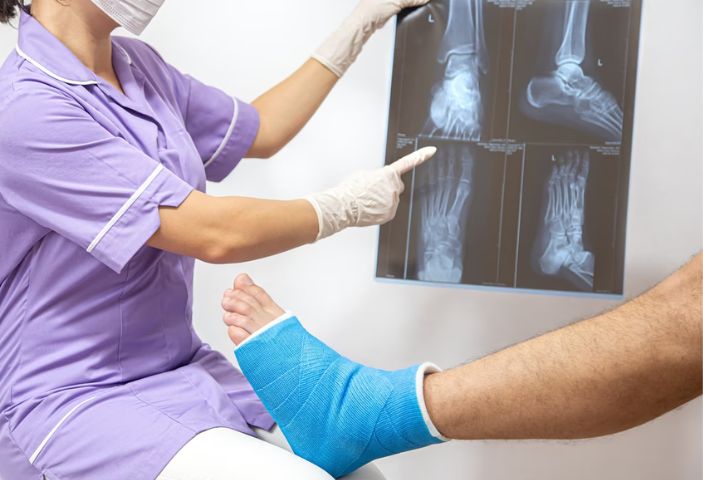

Gãy xương được chẩn đoán thông qua các triệu chứng kết hợp kết hợp với thực hiện các xét nghiệm, chẩn đoán hình ảnh.

- Thăm khám lâm sàng: phát hiện triệu chứng điển hình của gãy xương, phân loại gãy xương và đưa ra các chỉ định chẩn đoán hình ảnh tương ứng.

- Thực hiện kỹ thuật chẩn đoán hình ảnh (Xquang, CT, MRI): Phương pháp này tạo ra những hình ảnh hai chiều về xương, giúp bác sĩ xác định rõ các vết gãy, mức độ tổn thương xương, khớp, các cơ quan, phần mềm, mô, gân, cơ, dây chằng… lân cận và đưa ra phương pháp điều trị phù hợp.

- Xét nghiệm sinh hóa, xét nghiệm huyết học: đánh giá nguy cơ mất máu trong gãy xương, tình trạng nhiễm trùng vết thương giúp bác sĩ tiên lượng để có biện pháp điều trị an toàn.